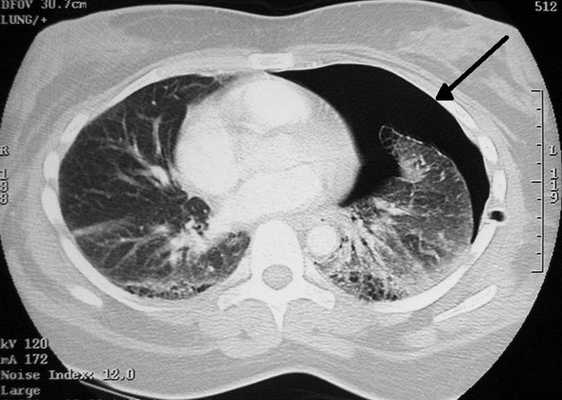

Пневмоторакс на снимке КТ (стрелка указывает на область, заполненную воздухом)

Томограммы отражают скопление газа в плевральной или грудной полости. При травмах по снимкам можно определить разрывы стенок кровеносных сосудов, очаги внутренних кровоизлияний и последствия геморрагий.